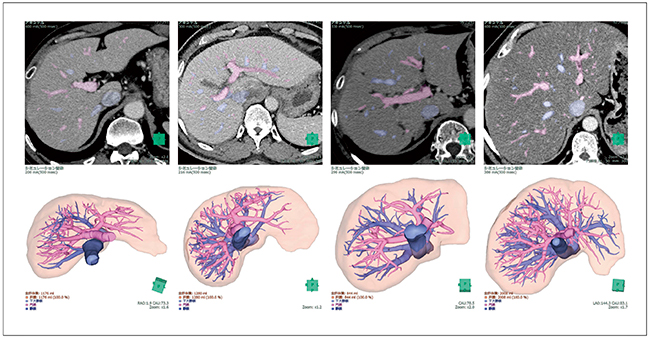

V5の最新バージョンおよびV6では,肝臓,下大静脈,門脈,肝静脈に対して,ディープラーニングを用いて設計した臓器抽出機能を追加した(図3)。

図3 肝臓,下大静脈,門脈,肝静脈抽出例

低SNR,造影効果,拡張胆管,脂肪肝など,さまざまな濃度・形状パターンに対して肝内の脈管系として認識する。